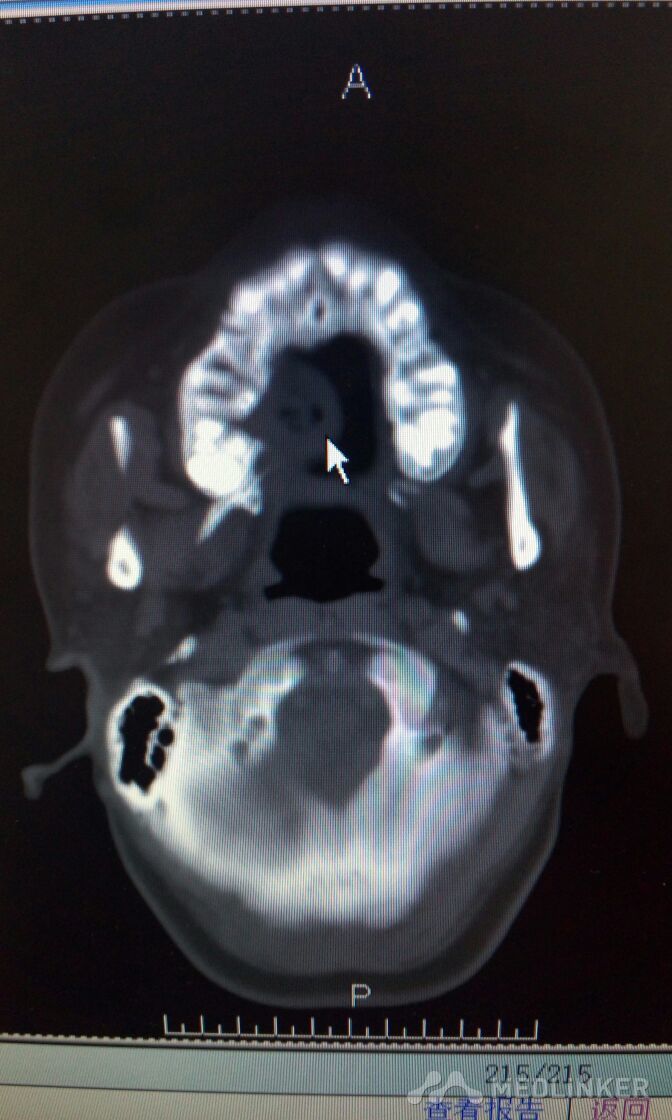

右侧上颌骨肿物,波及上颌窦,鼻腔。手术方案??

患者,女,38岁。因“发现右侧腭部肿痛一周”,来诊。查体:颌面部对称,张口度好。腭部右侧可见粘膜凸起肿物,约2*3cm,近中线处溃烂,有溢脓。CT检查可见肿物突入上颌窦及鼻腔,骨质破坏。现应用抗菌素治疗。拟行病理活检。请同仁看看手术方案?患者年轻,一侧上颌骨去除,假体如何修复?可否请鼻科联合手术,保留颌骨?